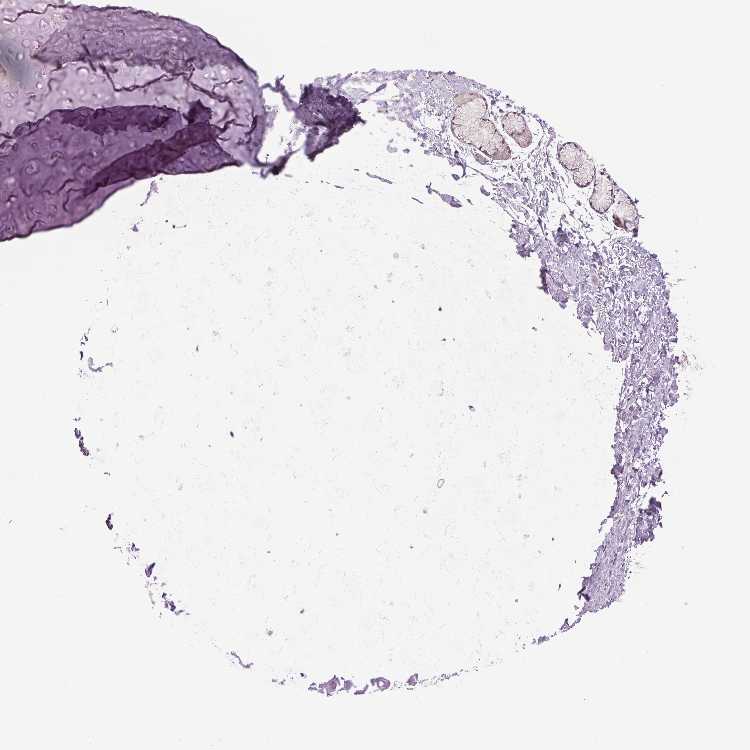

SOFT TISSUE 1 - Antibody stainingi

Antibody staining in the annotated cell types in the current human tissue is reported as not detected, low, medium, or high, based on conventional immunohistochemistry profiling in selected tissues. This score is based on the combination of the staining intensity and fraction of stained cells.

Each image is clickable and will lead to virtual microscopy that enables deeper exploration of all samples and also displays staining intensity scores, fraction scores and subcellular localization as well as patient and tissue information for each sample.

Antibody HPA056131

Chondrocytes Not detected

Fibroblasts Not detected

SOFT TISSUE 2 - Antibody stainingi

Peripheral nerve Not detected